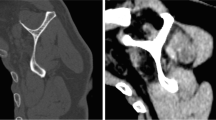

The skin and fascia of the torso and the pectoralis major and minor muscles were removed. The clavicle was disarticulated at the sternoclavicular and acromioclavicular joints and the brachial plexus, axillary vessels and their branches removed to expose the serratus anterior in its entirety (Fig. 1). The fascicular anatomy of the serratus anterior was described and quantified. A fascicle was defined as a bundle of muscle fibers with distinct and identifiable attachments to a rib. The muscle fiber angle of each fascicle was measured at the superior and inferior borders of each rib attachment using a flexible clear plastic goniometer (baseline 360°, measured to the nearest 1.0°). Muscle fiber angle was measured with respect to a vertical midline reference that passed through the suprasternal notch superiorly and the pubic symphysis inferiorly (Fig. 1). Starting from the caudal end of the serratus anterior, each fascicle was systematically detached from its respective rib and followed to its attachment on the scapula from which it was also removed. The sites of attachment were demarcated using colored ink (Cancer Diagnostics Inc., USA), photographed, measured and recorded. The length of the inferior aspect of each rib attachment site and its distance from the vertical midline reference were measured (to the nearest 0.1 cm) using a flexible tape to accommodate the curvature of the thorax (Fig. 2).

Lateral view of the right side of the thorax, clavicle removed and scapula displaced from the thoracic cage, showing the rib 1 (R1) to rib 8 (R8) fascicles of the intact serratus anterior muscle. Two fascicles attach to the superior (R2 S) and inferior (R2 I) aspect of the second rib. The R1 fascicle is partially obscured by the R2S fascicle on this view. The measurement of the muscle fiber angle, measured in situ using a flexible goniometer with respect to a vertical midline reference that passed through the suprasternal notch superiorly and the pubic symphysis inferiorly, is depicted for the measurement of the fiber angle at the superior aspect of the right rib 3 fascicle

Lateral view of the right side of the thorax, clavicle removed and scapula displaced from the thoracic cage, showing the rib 1 (R1) to rib 8 (R8) fascicle rib attachments demarcated by colored ink following removal of the serratus anterior muscle. The rib 2 inferior (R2 I) and superior (R2 S) fascicles attached along the inferior border of rib 2 and the superior aspect of rib 2 and first intercostal muscle, respectively. The measurement in situ of the length of each rib attachment and its distance from the vertical midline reference using a flexible tape measure is depicted for the right rib 4 fascicle